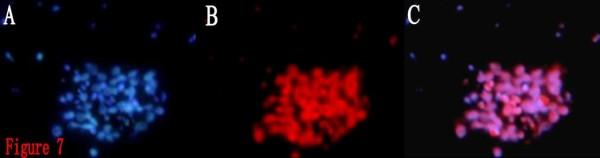

Limiting dilution and clonogenic assay were used to isolate and screen BTSCs from the fresh specimen of human brain glioblastoma. The obtained BTSCs, which were cultured in serum-free medium, were classified into four groups in accordance with the composition of the different treatments. The proliferation of the BTSCs was evaluated by MTT assay. The BTSCs were induced to differentiate in serum-containing medium, and classified into the ATRA group and control group. On the 10th day of induction, the expressions of CD133 and glial fibrillary acidic protein (GFAP) in the differentiated BTSCs were detected by immunofluorescence. The differentiated BTSCs were cultured in serum-free medium, the percentage and the time required for formation of brain tumor spheres (BTS) were observed.

BTSCs obtained by limiting dilution were all identified as CD133-positive by immunofluorescence. In serum-free medium, the proliferation of BTSCs in the ATRA group was observed significantly faster than that in the control group, but slower than that in the growth factor group and ATRA/growth factor group, and the size of the BTS in the ATRA group was smaller than that in the latter two groups(P < 0.01). In serum-containing medium, the expression percentages of CD133 and GFAP in the differentiated BTSCs were (2.29% +/- 0.27%) and (75.60% +/- 4.03%) respectively in the ATRA group, and (7.05% +/- 0.49%) and (12.51% +/- 0.77%) respectively in the control group. The differentiation rate of BTSCs in the ATRA group was significantly higher than that in the control group (P < 0.05), but there was still CD133 expressed in the ATRA group. The differentiated BTSCs could re-form BTSs in serum-free medium. The percentage of BTS formation in the ATRA group was(4.84% +/- 0.32%), significantly lower than that in the control group (17.71% +/- 0.78%) (P < 0.05), and the time required for BTS formation in the ATRA group was (10.07 +/- 1.03)d, significantly longer than that in the control group (4.08 +/- 0.35)d (P < 0.05).

通过有限稀释获得的 BTSCs 均通过免疫荧光鉴定为 CD133 阳性。在无血清培养基中,ATRA 组 BTSCs 的增殖速度明显快于对照组,但慢于生长因子组和 ATRA/生长因子组,ATRA 组的 BTS 体积小于后两组(P < 0.01)。在含血清培养基中,ATRA 组分化后的 BTSCs 中 CD133 和 GFAP 的表达百分比分别为(2.29% ± 0.27%)和(75.60% ± 4.03%),对照组分别为(7.05% ± 0.49%)和(12.51% ± 0.77%)。ATRA 组 BTSCs 的分化率明显高于对照组(P < 0.05),但 ATRA 组仍有 CD133 表达。分化后的 BTSCs 可在无血清培养基中重新形成 BTS。ATRA 组 BTS 形成的比例为(4.84% ± 0.32%),明显低于对照组的(17.71% ± 0.78%)(P < 0.05),ATRA 组形成 BTS 的时间为(10.07 ± 1.03)d,明显长于对照组的(4.08 ± 0.35)d(P < 0.05)。